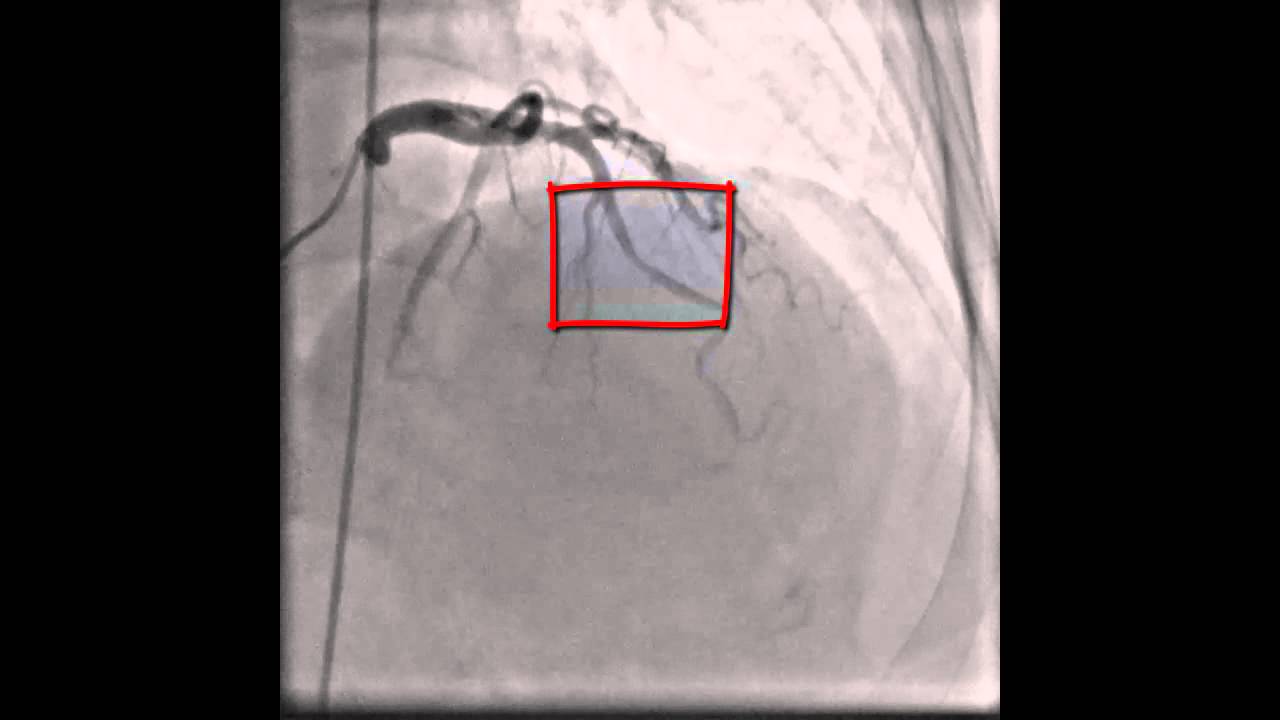

From www.radcliffecardiology.com

Figure 3 Case Example of Induced Coronary Spasm with Acetylcholine Spasm In Your Heart It is chest tightness or pain caused by tightening of a heart artery. This causes part of the blood vessel to narrow. Coronary artery spasms happen when the walls of blood vessels squeeze together. These symptoms may occur spontaneously or due to cold weather, exercise or stress. There can also be arm or jaw pain. What is a coronary artery. Spasm In Your Heart.